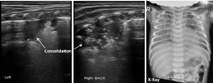

本组MAS患儿的肺脏超声主要表现(表1):(1)肺实变伴支气管充气征:见于所有患儿,重度患儿通常为范围较大、且边界不规则(锯齿状边缘)的实变区(图2,图3,图4);而轻度患儿则以小范围的局限性实变为主要表现(图5);但双侧肺脏实变范围的大小可以不同,而且同一侧肺脏野可以存在大小不同的实变区(图4,图5,图6)。(2)胸膜线异常与A-线消失,见于所有患儿,胸膜线异常表现为病变区胸膜线消失或增粗模糊(图2,图3,图4,图5,图6)。(3)肺不张,是严重肺实变的表现,见于重度患儿,本组12例(17.9%)(图7),严重大面积肺不张时可在实时超声下见到肺搏动和动态支气管充气征。(4)胸腔积液,见于9例(13.4%)患儿(图7)。(5)B-线或AIS,在实变区以外肺野则以AIS或B-线为主要表现。

MAS具有典型的肺脏超声影像学改变。主要特征如下:(1)肺实变伴支气管充气征,见于所有患儿。通常重度患儿实变范围较大、边界不规则呈锯齿状,支气管充气征也较为明显;而轻度MAS则为较小范围的局灶型实变。(2)双侧肺脏或同一侧肺脏不同肺野病变性质与程度的不一致性,双侧肺脏可有范围不同的实变区,同一侧肺脏不同肺野也可以存在大小不同的实变区。(3)肺不张,见于少数重症患儿,更为严重者在实时超声下可见肺搏动或动态支气管充气征。(4)胸膜线异常,表现为病变区胸膜线消失或增粗、模糊。(5)A-线消失,所有患儿在实变区和非实变区均不见A-线。(6)B-线或AIS,非实变区肺组织在超声下常表现为B-线或AIS。(7)胸腔积液,轻度或重度MAS患儿均可有胸腔积液,本组见于13.4%的患儿。但上述超声表现也可见于RDS、肺不张和TTPN等肺病,虽均非MAS的特有改变,但均有各自的特点,超声很容易对它们做出诊断和鉴别诊断[4,5,6,7]。但在肺炎、尤其重度肺炎时,肺脏超声也表现为边界不规则的大面积肺实变[7,15],如无一定经验,仅靠超声表现有时难以将二者准确区别。因此,在借助超声诊断MAS与重症感染性肺炎时,往往需要结合病史。